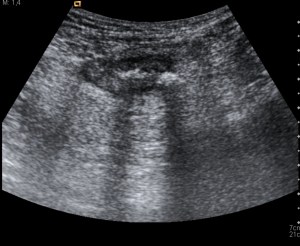

ECOGRAFÍA DE ABDOMEN: Engrosamiento mural a nivel de sigma, con presencia de divertículos y discreta hiperecogenicidad de la grasa adyacente. Se observan dos focos brillantes hiperecogéncios con sombra acústica sugerentes de fecalitos. Estos hallazgos son compatibles con diverticulos inflamados con fecalitos en su interior.

ECOGRAFÍA – Divertículos = Imágen redondeada hiperecogénica + Cambios inflamatorios (Grasa hiperecogénica ó Halo hipoecogénica peridiverticular) + Engrosamiento mural > 4 mm + Fecalitos (Imágen hiperecogénica con sombra posterior) + Signos de complicación (Absceso, perforación o fístula).